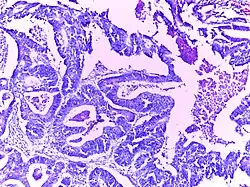

Adenocarcinoma stomach | Micrograph of carcinoma stomach. The glands are seen infiltrating the muscle layer. The neoplastic cells are arranged in cords and in glandular pattern. The cells show dysplastic features. Signet rings with nucleus pushed to the periphery are seen in some types of adenocarcinoma. | Category: Histopathology of adenocarcinoma stomach | Adenocarcinoma of stomach |

![]() |